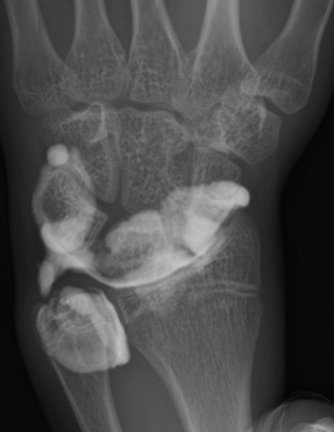

単純X線の他、MRI、手関節造影/CTを行います。単純X線では、TFCC自体は映りません。しかし、骨形態の評価、とくに突き上げ症候群の評価に有用であり、必須の検査の1つです。MRIではTFCCの損傷の有無を評価します。また、ECU腱鞘炎などその他の障害/疾患の有無を確認します。しかしながら、MRIではTFCCの詳細な評価が難しい場合があり、手関節造影/CTが必要となることがあります。手関節造影/CTでは、造影剤を橈骨手根関節内および遠位橈尺関節内に注入しTFCCの円盤部や末梢部、表層部、および小窩(Fovea)部などでの断裂形態を確認します。その他、手根骨間靱帯損傷や手関節尺側部の骨形態について評価します。

【手関節造影】